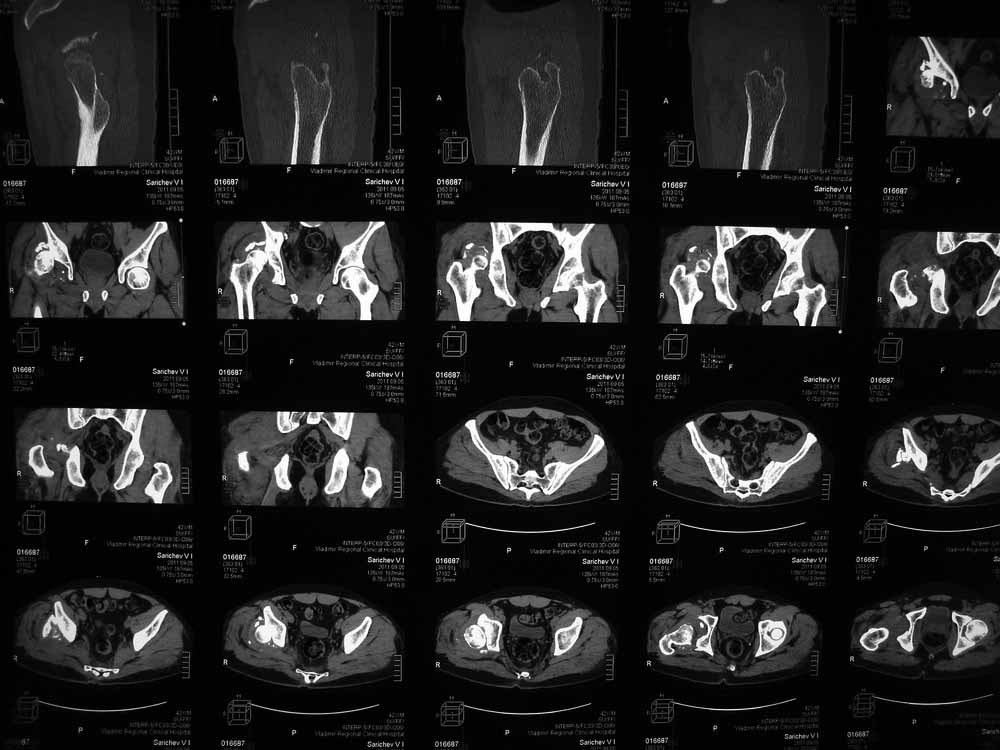

42 года, майор запаса. Травма от 20.06 - ДТП. Лечился в гражданском ЛПУ. Вывих бедра диагностирован только 4 недели спустя. "Тянулся", неоднократно - попытки закрытой репозиции. Попытка открытой репозиции - без результата. Потом опять пытались закрыто, сказали, что вправили, тянулся. После снятия ССВ - опять вывих. Поступил к нам. Сейчас - СРБ больше 10, в ОАК - воспаление. Местно - головка кзади и кверху, укорочение 7, голова подвижна. Отек, незначительная боль в в/3 бедра. Пассивно из наружной ротации выводится, активных движений в ноге нет. Рубец по наружной поверхности верхней трети бедра, без воспаления. Каким образом выполнялось открытое вправление - данных нет. Окончательно снят с вытяжения 2 недели назад.

Структуру головки не очень хорошо видно, есть перелом нижнего отдела головки БК, сломанный задний край небольшой. Срок после травмы 4 недели, молодой возраст. Есть смысл синтезировать ВВ, а дальше посмотреть. Будут проблемы - легче будет протез ставить, ну а если лет 8-10 сустав поработает, то и это хорошо. Если вы уж решили делать протезирование, не мудрите, вполне можно обойтись стандартной вертлужной впадиной с укреплением ее винтами.

В этой ситуации предпочел бы эндопротез, шансы на жизнеспособность головки в таком сроке вывиха исчезающе малы, попытка синтезировать задний край в этих же сроках (ретракция мышц, рубцы) скорее всего приведут к его девитализации с последующим аваскулярным некрозом. Выбор вертлужного компонента проще планировать после 3D, скорее всего можно будет обойтись стандартными предложением, возможно, с котилопластикой.